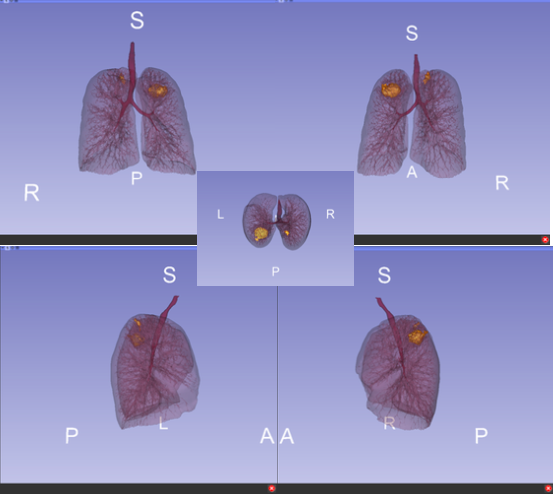

Volumetric Visualisation is a module of the Med Vis course and teaches students about the creation of 3D renders from 2D, traditional scan data such as CT and MRI scans.

I gained skills in both indirect and direct volume rendering as well as data registration (the alignment of data) and produced a high quality assignment utilising these skills. This assignment provided me with a deeper understanding as to what technique to choose when faced with a problem, a skill which I adopted during the development of my MSc project when creating vertebrae models.